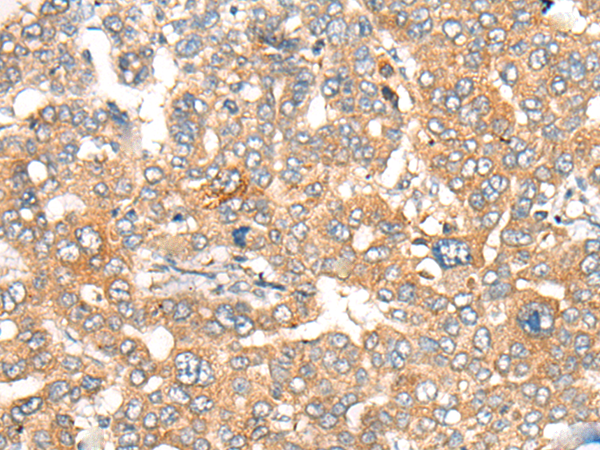

IHC positive control: |

Human liver cancer and human cervical cancer |

IHC Recommend dilution: |

30-150 |